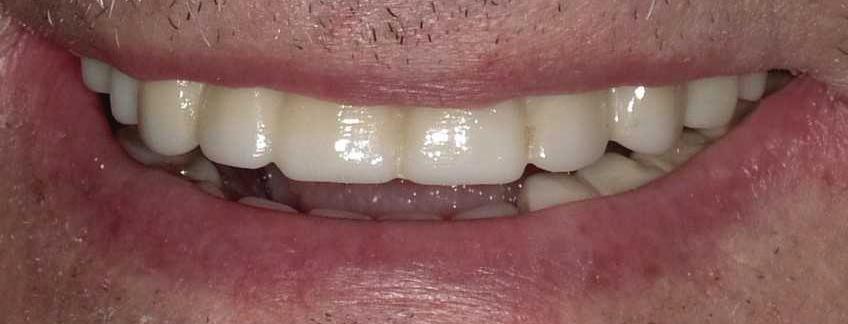

Can just four implants replace all of the teeth on the top or the bottom of your mouth? Thanks to advances in dental implant technology, that answer is a resounding yes.

Believe it or not, tooth loss is extremely common among adults, especially as we age. In fact, more than 35 million people in America are missing all of their upper and/or lower teeth. Rather than living with the discomfort and hassles of dentures, many people are opting for what is called “all-onfour” dental implant restoration.

All-On-Four: One Full Arch Of Teeth, Four Dental Implants

A Reason To Smile Again

able technique for replacing teeth, you should first understand what a dental implant is. An implant is a small titanium screw that fits inside your jawbone and replaces the root-part of a missing tooth. Minor surgery is required to insert the implants. Once the implant is in place, a crown is attached to give you a highly realistic-looking and functional prosthetic tooth.

Here’s where it gets really interesting: You do not need a dental implant for each and every one of your missing teeth. All you need is four precisely placed implants on the top of your mouth, and four on the bottom, to restore your full smile. That’s the beauty of the all-on-four. And because the implant is made of titanium, it has the unique ability to fuse to living bone and function as part of it. So eventually, the dental implant becomes part of the jawbone and serves as a strong, long-lasting foundation for your new teeth.

Besides ensuring that your implants are permanently fixed in place,

this bone fusion has another important benefit: it prevents future bone loss in the jaw. This helps to maintain a more youthful facial structure – and better oral health. But perhaps the biggest surprise about the all-on-four is how quickly it can transform your life.

All-On-4 Dental Implants: A Reason To Smile Again

To fully understand this remarkable technique for replacing teeth, you should first understand what a dental implant is. An implant is a small titanium screw that fits inside your jawbone and replaces the root-part of a missing tooth. Minor surgery is required to insert the implants. Once the implant is in place, a crown is attached to give you a highly realistic-looking and functional prosthetic tooth.

Besides ensuring that your implants are permanently fixed in place, this bone fusion has another important benefit: it prevents future bone loss in the jaw. This helps to maintain a more youthful facial structure – and better oral health. But perhaps the biggest surprise about the all-on-four is how quickly it can transform your life.